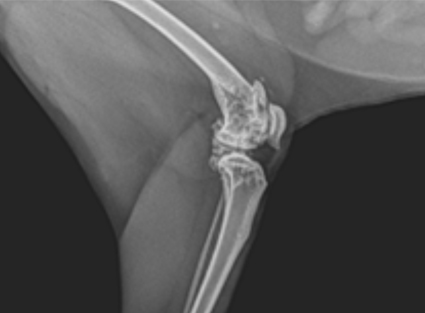

Radiología Ortopédica

- Diagnóstico de fracturas

- Displasia de cadera y codo

- Enfermedades articulares

- Evaluación prequirúrgica y postquirúrgica